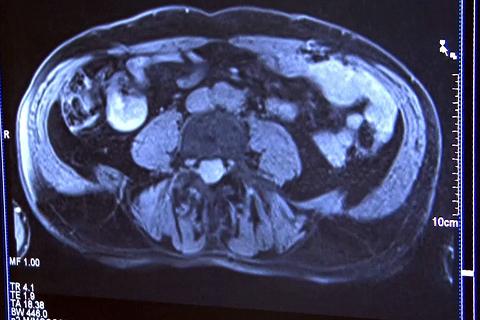

Imagine IRM, Foto: Hotnews

​VIDEO Cum functioneaza un aparat de rezonanta magnetica. Cat de puternica este forta magnetului? Poate depista cancerul?

​In 1977 a fost efectuata prima examinare a unei persoane cu ajutorul rezonantei magnetice, iar producerea imaginii a durat 5 ore cu acest aparat care a fost numit „Indomitable”. Dupa cateva decenii imagistica prin rezonanta magnetica (IRM) sau Rezonanta magnetica nucleara (RMN) a devenit o investigatie care ofera informatii mai precise decat radiografia, ecografia sau tomografia computerizata pentru diagnosticul accidentelor vascular cerebrale, artritei si tumorilor. Va prezentam principiul de functionare, ce afectiuni se pot depista si cum trebuie sa te pregatesti pentru investigatie.